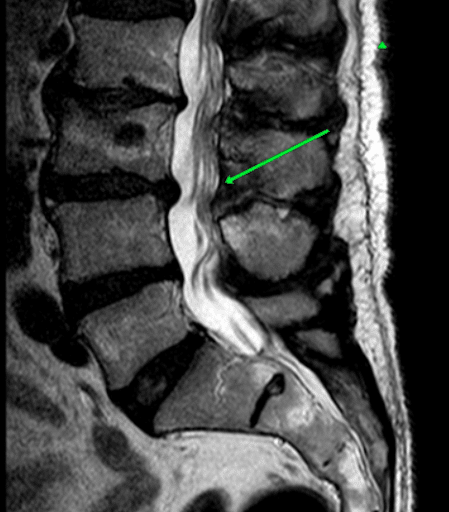

Stan po leczeniu operacyjnym

Widoczne usunięte więzadło żółte. Nie ma zwężenia kanału kręgowego pomiędzy kręgami L3 i L4.